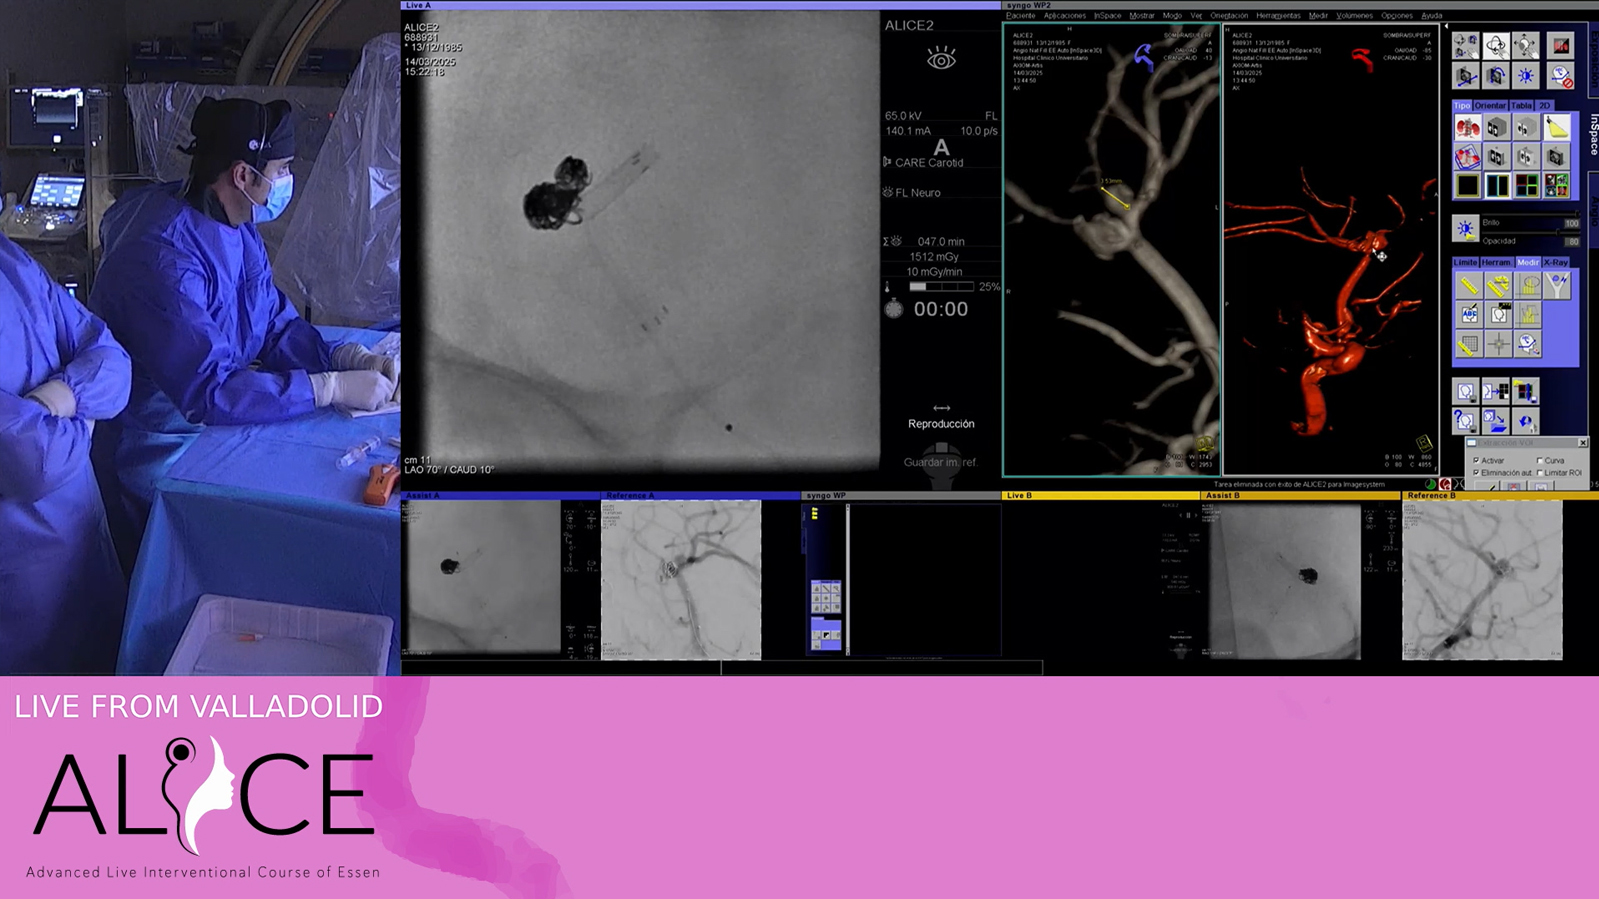

Valladolid: Aneurysm

ICA Dissection treated by Stenting with Wallstent

Postcentral AVM treated by transvenous embolization

Distal M2 occlusion thrombectomy with embotrap

Fusiform ICA Aneurysm treated by kissing flowdiverter

SCA Aneurysm to be treated by "Chanel" stenting

Frontal AVM treated by transvenous embolization

Cerebellar AVM treated by venous pressure cooker embolization